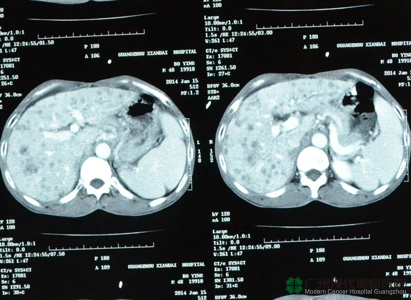

ครอบครัวคุณอินและเพื่อนๆ ให้กำลังอยู่ข้างๆ เขาตลอด พวกเขาวิ่งวุ่นไปทุกๆ ที่ เพื่อค้นหาการรักษาที่ดียิ่งกว่าให้แก่คุณอิน ต่อมามีเพื่อนคนหนึ่งแนะนำให้เขาไปรักษาที่ประเทศจีน เนื่องจากประเทศจีนมีโรงพยาบาลที่รักษามะเร็งโดยเฉพาะ---โรงพยาบาลมะเร็งสมัยใหม่กว่างโจว และมีสำนักงานอยู่ที่กรุงเทพประจำประเทศไทย คุณอินจึงโทรศัพท์ไปสอบถามที่สำนักงานเพื่อทำความเข้าใจ ซึ่งพอดีกับที่มีเจ้าหน้าที่ของเราไปปฏิบัติงานที่เชียงใหม่ จึงสามารถพูดคุยกับเขาโดยตรง หลังจากที่ฟังเจ้าหน้าที่อธิบายอย่างละเอียด เขาได้ทราบเทคโนโลยีการรักษาที่ทันสมัยผลข้างเคียงน้อย เห็นผลเร็ว ครั้นแล้วเขาจึงมีความหวัง คุณอินจึงได้มาที่โรงพยาบาลมะเร็งสมัยใหม่กว่างโจว แพทย์ได้ทำการตรวจทุกด้าน และประชุมร่วมกับทีมผู้เชี่ยวชาญ จึงได้กำหนดวิธีการรักษาตามสภาพความเป็นจริง และตัดสินใจทำการักษาแบบบูรณาการ โดยใช้วิธีหลักๆ คือการรักษาแบบเฉพาะจุดผ่านหลอดเลือด นั้นเป็นวิธีการรักษาที่ไม่เคยไม่ยินในประเทศไทย บาดแผลเล็ก ผลข้างเคียงน้อย หลังจากทำการรักษาแบบเฉพาะจุดผ่านหลอดเลือดสองครั้ง ผลซีทีสแกนปรากฏว่าเนื้อร้ายมีขนาดเล็กลง อาการที่รู้สึกไม่สบายก็หายไป น้ำหนักก็เพิ่มขึ้นเป็น 52กิโลกรัม เขารู้สึกว่าตนเองกลับมาเป็นเหมือนคนปกติอีกครั้ง คุณอินบอกเราอย่างดีใจ

ผลซีทีสแกนก่อนการรักษา